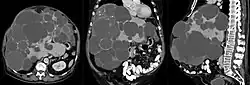

Als Zystenleber, auch polyzystische Leber oder zystische Leberkrankheit genannt, bezeichnet man eine meist angeborene Fehlbildung der Leber, bei der dieses Organ mit einer Vielzahl von flüssigkeitsgefüllten Hohlräumen (Zysten) durchsetzt ist. Die Zystenleber wird zu den gutartigen (benignen) Tumoren gezählt.

Bei vorhandenen Symptomen erfolgt die Diagnose mittels bildgebender Verfahren, meist mittels Ultraschall oder Computertomographie. Da die Mehrzahl der polyzystischen Lebererkrankungen genetisch bedingt ist, spielt auch eine eingehende Familienanamnese eine wichtige Rolle.

- Abbildung einer Zystenleber im CT